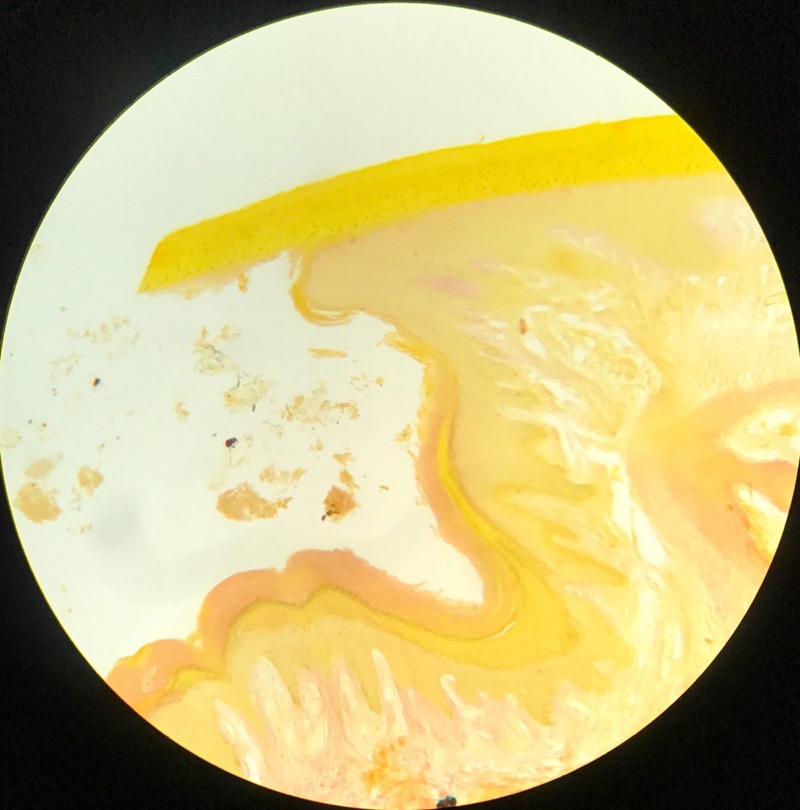

| 1:5:6 | Nagel | ![]() ![]() ![]() ![]() ![]() |